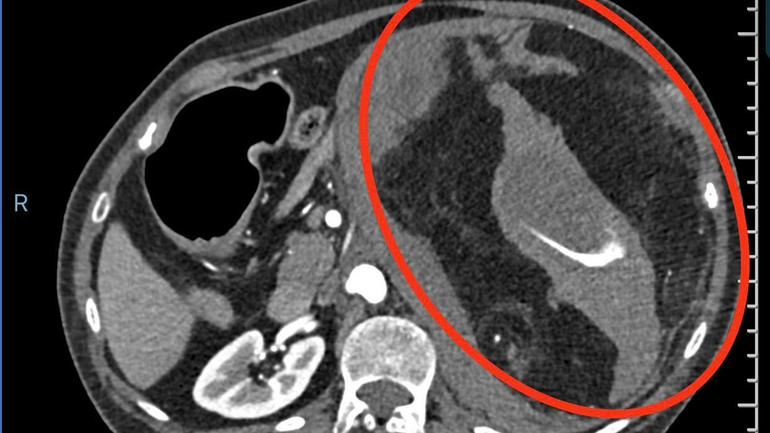

Bệnh nhân B. 67 tuổi, ngụ tỉnh Tây Ninh bị u cơ mỡ mạch thận bên trái, loại u lành tính thường gặp ở phụ nữ trung niên. Khối u thận có kích thước khổng lồ lên đến 16cm, bất ngờ vỡ khiến bà B. bị đau dữ dội, tụt huyết áp, rơi vào trạng thái sốc mất máu đe dọa đến tính mạng.

hinh-anh-ct-scan-khoi-buou-gay-xuat-huyet.jpg

Hình ảnh scan khối bướu gây xuất huyết.